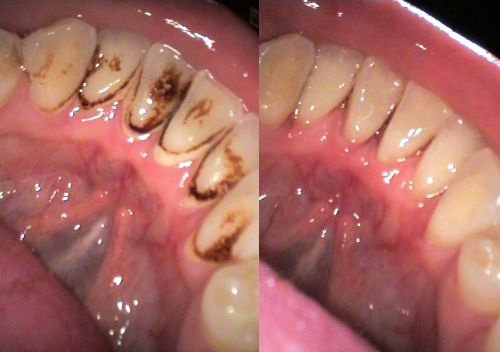

Consultatie+detartraj+periaj+airflow la numai 50RON

Va oferim un pachet de consultatie, plan de tratament, detartraj,periaj profesional si airflow la numai 50 RON in loc de 150 RON. Oferta de albire dentara este valabila numai luna Aprilie. Pentru detalii va rugam sa sunati la numarul de telefon...